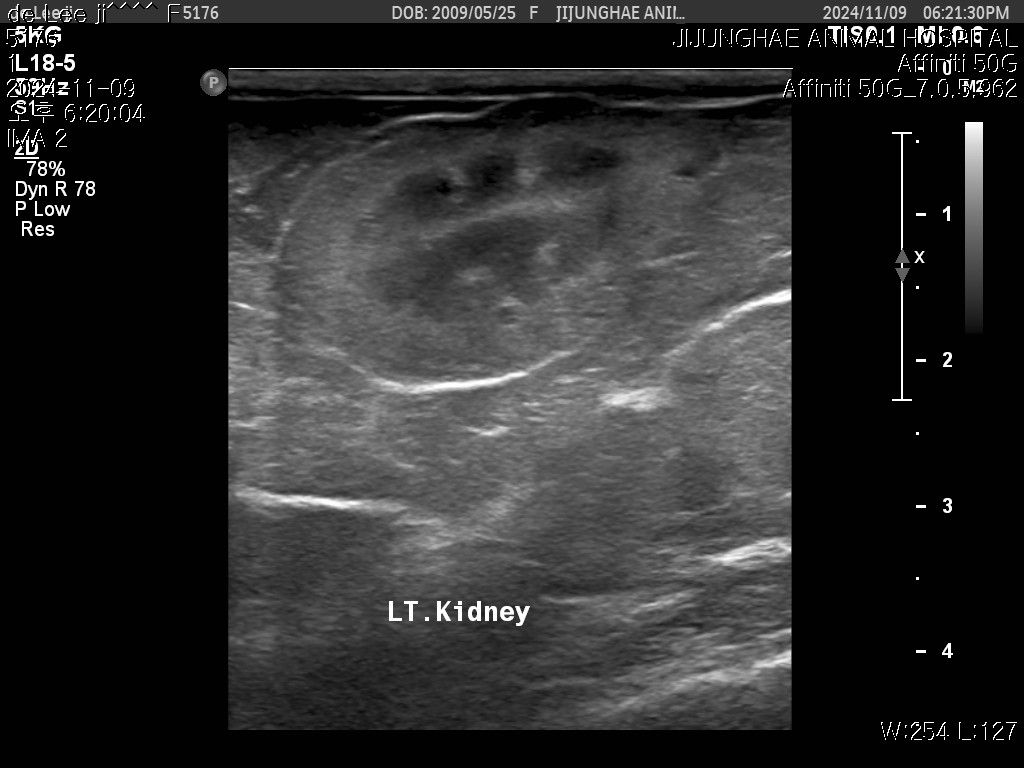

작년 검진때도 듣긴했는데 올해 다시 초음파를보니

키위모양으로 있던데..찾아보니 키위모양이 많이위험하다고들었습니다

초음파사진 같이첨부하니 아이의 점액종 상태가

어떤지좀 봐주세요 제발부탁드립니다 !!!🙏